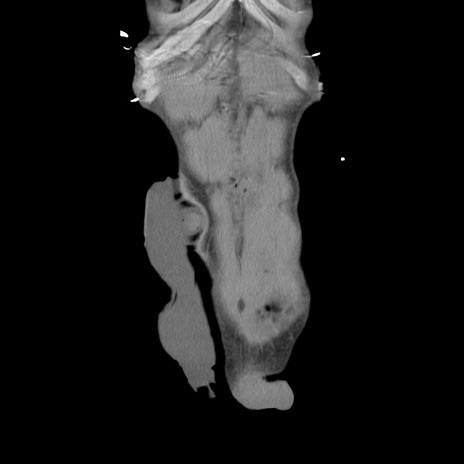

症例11(冠状断像)

【症例】 60歳代男性

【主訴】 下腹部痛

【現病歴】 本日夜中より下腹部痛の症状認め、受診。

【既往歴】 膀胱癌(膀胱全摘+尿管皮膚瘻術) 、胃癌術後

【身体所見】 BT 35.3℃、PR 58/min、BP 136/98mHg、腹部平坦、軟、腸蠕動音±、ストマ留置あり、左上腹部~正中部に圧痛あり、反跳痛なし。

【データ】WBC 5100、CRP0.01